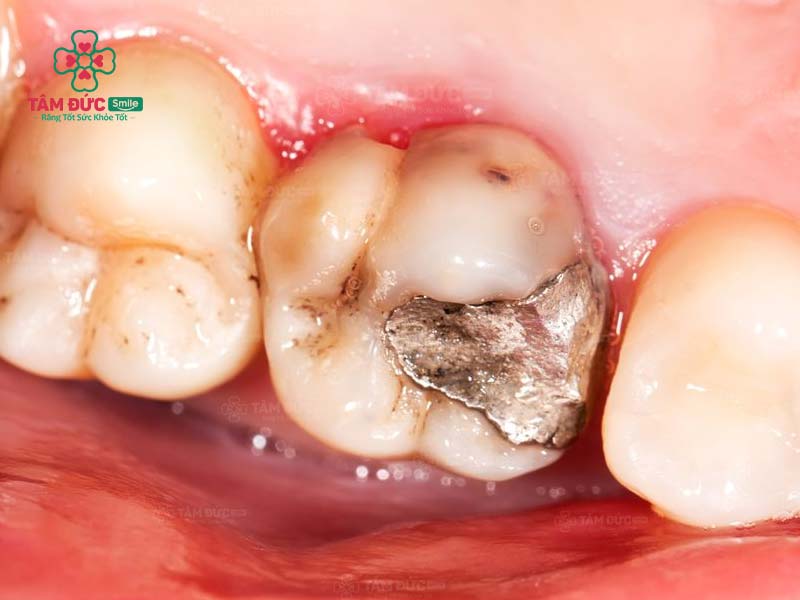

1.4. Thay miếng trám mới

Hiệu quả trám răng không thể duy trì vĩnh viễn. Theo thời gian, miếng trám răng cũ có thể bị bong tróc hoặc rơi ra do tác động từ lực ăn nhai. Trong trường hợp này, bác sĩ sẽ yêu cầu thay miếng trám răng mới.

răng trám cũ và răng trám mới

Quý khách cần trám lại răng khi miếng trám cũ bị bong tróc